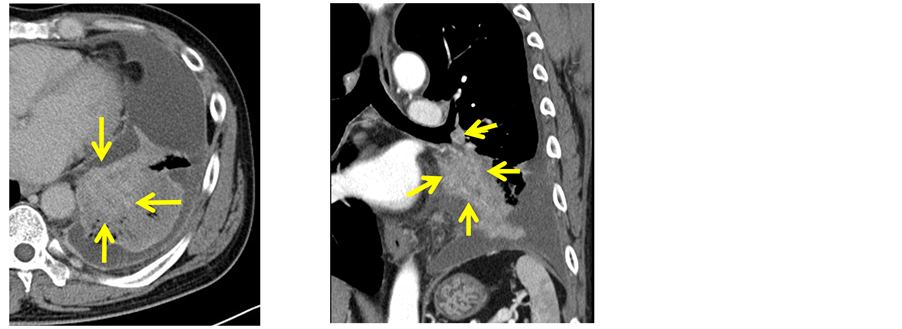

In June 2010, a 48-year-old male with exertional dyspnea was admitted to a hospital and a left massive pleural effusion was indicated on X-ray film (Figure 1). A chest drainage tube was inserted and hemorrhagic effusion was confirmed with a total volume of 1500 ml. However, the cytological examination showed no malignancy. A bronchoscopic examination revealed endobronchial stenosis of the left lower bronchus B8,9,10 (Figure 2(A)) and slight discontinuous bleeding; the biopsy resulted in the diagnosis of pulmonary angiosarcoma. Extrabronchial invasion was suspected at the left main endobronchial membraneous portion (Figure 2(B)). In the right B6 (Figure 2(C)), a squamous cell carcinoma in situ was pathologically diagnosed, which had been under observation.

Figure 1. Chest X-ray showing the left massive pleural effusion.